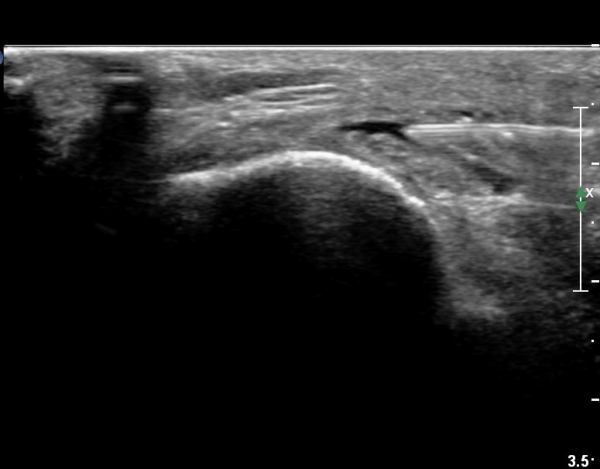

ŽÃËÀÚ¸¦ Á» ´õ ¸»´Ü, ¿ÜÃøÀ¸·Î À̵¿ÇÏ´Ï ºñ°ñµÎ Ç¥Ãþ¿¡¼­ ºñ°ñ½Å°æÀÌ Àú¿¡ÄÚ·Î °üÂûµÈ´Ù(»çÁø 3, 4, 5).

ŽÃËÀÚ¸¦ Á» ´õ ¸»´ÜÀ¸·Î À̵¿ÇÏ´Ï ºñ°ñ °æºÎ Ç¥Ãþ¿¡¼­ ºñ°ñ½Å°æÀÌ °üÂûµÇ°í(»çÁø 6, 7),